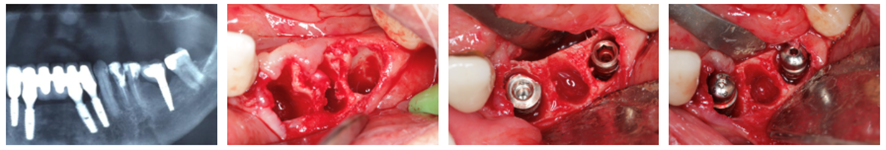

Para todas as situações clínicas

“A nova linha é excelente para implante imediato pós-extração. Venho utilizando sistematicamente nos casos de regeneração óssea guiada, principalmente nos aumentos verticais. Um diferencial é o fato desse implante possuir no topo uma parte de metal polido (0,25 mm de altura), sobretudo para casos de aumento vertical, onde não temos um controle de como e o quanto esse novo osso vai remodelar. Aliado a tudo isso, há a plataforma switching que tem como benefício afastar o microgap entre a conexão e o implante dos tecidos peri-implantares, minimizando as perdas causadas pelo infiltrado bacteriano e contribuindo para a estabilidade do osso marginal ao redor do implante.”

“A tecnologia do implante cone-morse Maestro (macrogeometria e plataforma switching) agora está presente nos implantes Hexágono Interno e Externo. Eu utilizo implante cone-morse, mas agora existe a possibilidade de utilizar os implantes de conexões hexagonais com maior segurança na osseointegração. A plataforma switching presente nos implantes HE e HI Switch permite, em algumas situações, que possamos inserir os implantes ligeiramente abaixo da crista óssea, beneficiando assim a formação óssea ao seu redor, protegendo o implante e respeitando o espaço para uma melhor neoformação do osso e do tecido mole.”